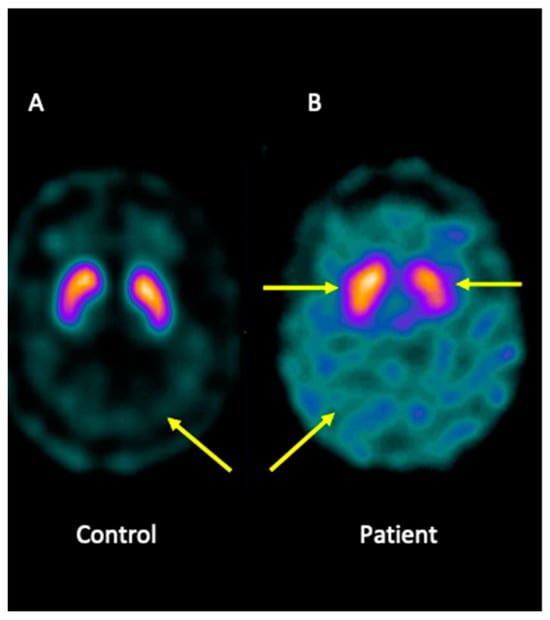

4.2. Analysis of the Brain Imaging with Single-Photon Emission Computed Tomography